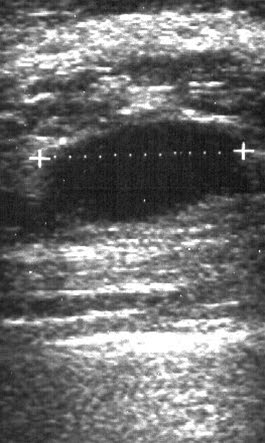

Ultralyd mamma, cyste

Cysten i brystkjertelen vises som en ekkofri velavgrenset oval struktur